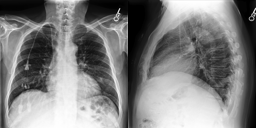

CheXpert

The CheXpert dataset [32] has 224,316 chest X-ray images of size 390320 from 64,540 patients. Images may have multiple labels, where the possible labels correspond to five pathology classes: ‘Cardiomegaly’, ‘Edema’, ‘Consolidation’, ‘Atelectasis’, and ‘Pleural Effusion’. In our work, following prior state-of-the-art training, we re-scale all images to size 224224 and augment the dataset using random affine transformations [69, 70].